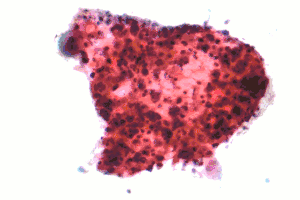

| Micrograph of a squamous carcinoma, a type of nonsmall-cell lung carcinoma, FNA specimen, Pap stain. | |

The most common types of NSCLC are squamous-cell carcinoma, large-cell carcinoma, and adenocarcinoma, but several other types occur less frequently. A few of the less common types are pleomorphic, carcinoid tumor, salivary gland carcinoma, and unclassified carcinoma.[4] All types can occur in unusual histologic variants and as mixed cell-type combinations.[5] Nonsquamous-cell carcinoma almost occupies the half of NSCLC. In the tissue classification, the central type contains about one-ninth.

Squamous-cell lung carcinoma

Squamous-cell carcinoma (SCC) of the lung is more common in men than in women. It is closely correlated with a history of tobacco smoking, more so than most other types of lung cancer. According to the Nurses' Health Study, the relative risk of SCC is around 5.5, both among those with a previous duration of smoking of 1 to 20 years, and those with 20 to 30 years, compared to "never smokers" (lifelong nonsmokers).[12] The relative risk increases to about 16 with a previous smoking duration of 30 to 40 years, and roughly 22 with more than 40 years.[12]